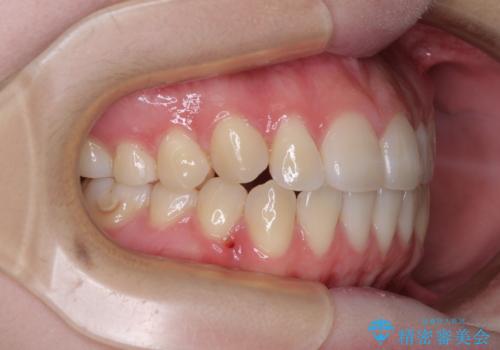

カリエール・ディスタライザーとインビザラインを用いた八重歯の改善

- 前歯の叢生と上顎左右の八重歯を気にして来院された患者様です。

奥歯の咬み合わせを見ると、左側は上顎が下顎に対して相対的に前方にあり、上下の前歯が接触していない状態でした。

咬み合わせを改善するためには、左側上顎臼歯を後方に移動させた咬み合わせにする必要があります。

インビザライン単体で改善することも可能性もありますが、インビザライン単体で達成する可能性が低いと考えられたため、カリエール・ディスタライザーという補助装置を併用して、より確実性を上げることとしました。

奥歯の咬み合わせを改善しながら、並行してインビザラインで歯列を整えることとしました。

カリエールディスタライザーを併用したことで、左側臼歯の咬み合わせを確実に改善させることができました。